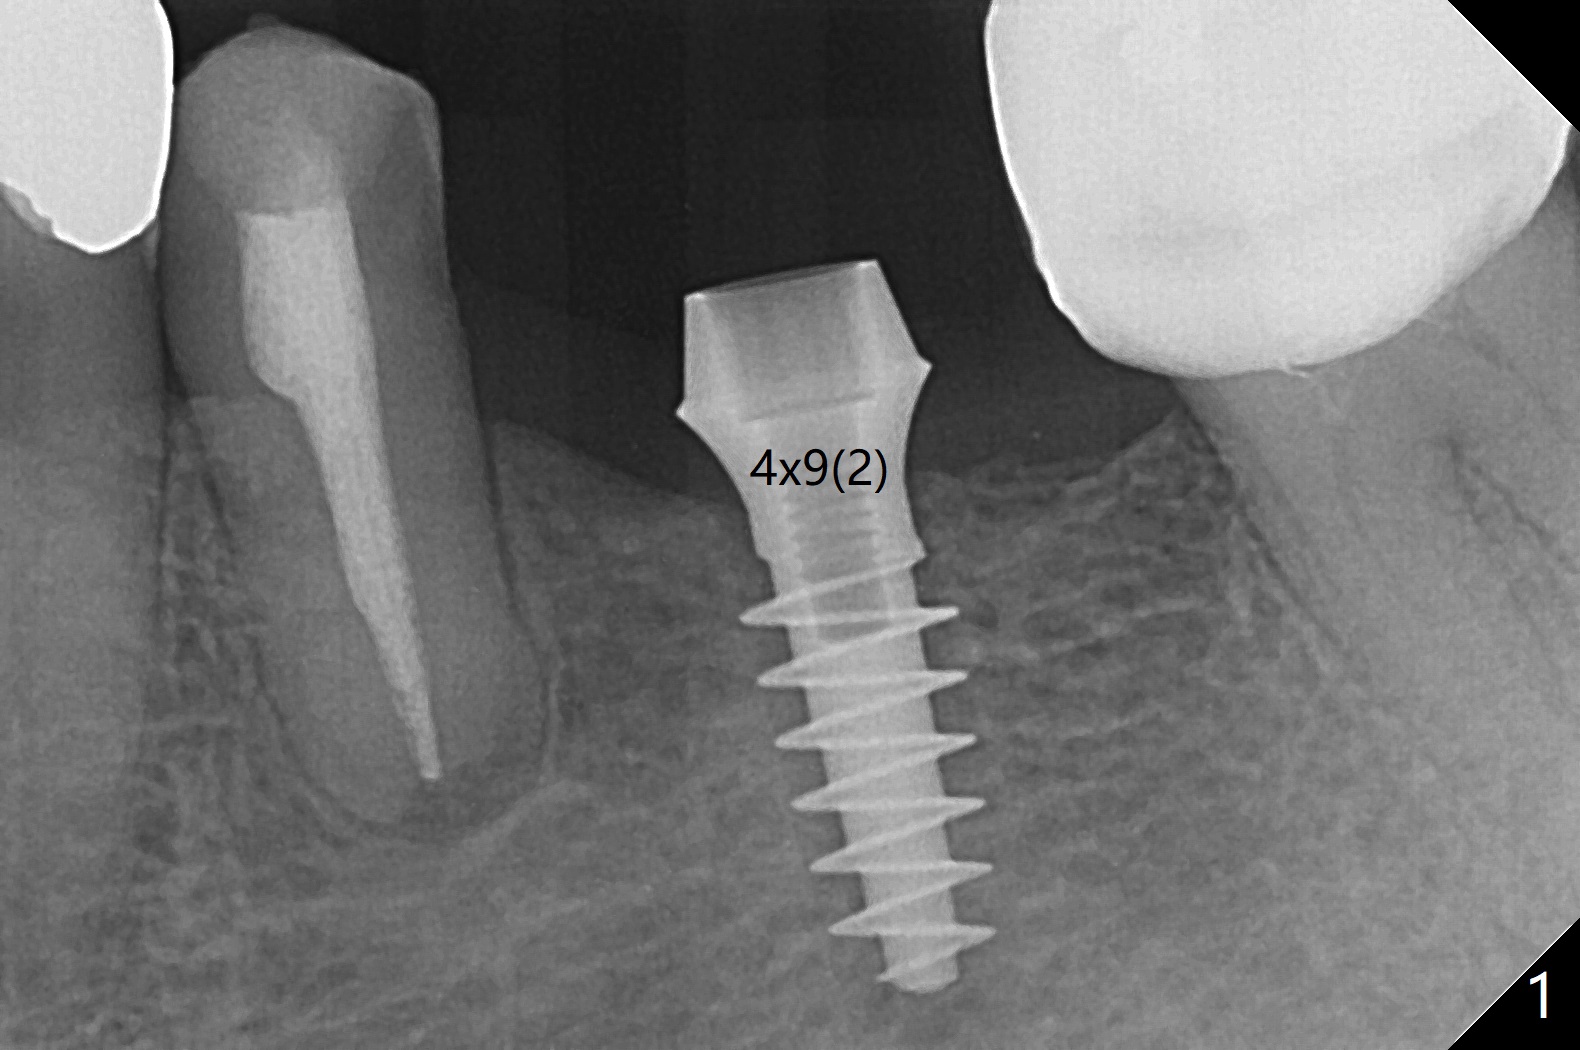

After finishing osteotomy at #19 according to IS drill sequence for 4x10 mm implant except cortical tap, a 4x9(2) mm Magicore is placed with ~ 50 Ncm (Fig.1). A 4.5x3 mm solid abutment is placed to check occlusion (Fig.2). There is discrepancy in osteotomy depth probably due to difference between the implant systems or overprep for subcrestal placement (narrow ridge, Fig.2 *). The implant could be 2 mm longer or the cuff could be longer (3 mm instead of 2 mm). The implant with 4.5x3 mm solid abutment is stable for impression nearly 3 months postop (Fig.3). Appreciate the distinct thread pattern of Magicore 3 months 1 week postop, immediately post cementation (Fig.4). Bone density increases 7 months post cementation (Fig.5 *). There is less likely implant fracture associated with a 1-piece one than a 2-piece one when a narrow one is placed in the narrow ridge.